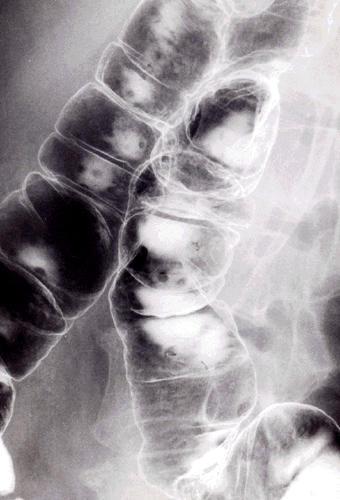

疾病(病理主体)的分类恶性淋巴系统・血液系统肿瘤/ATL (成人,ATL细胞白血病)

部位(按器官分)大肠/占据大肠的2个以上区域

检查方法X线